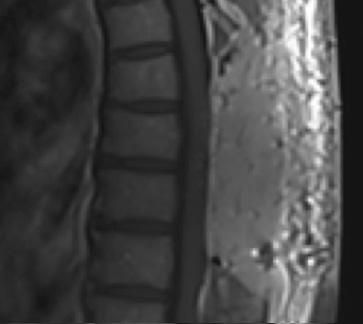

Postoperative MRI T1w demonstrating a gross total resection

Postoperative MRI T1w demonstrating interval resection with cord re-expansion (blue arrow)

Pathology came back as Atypical Meningioma, WHO grade 2. Postoperative MRI showed a gross total resection without residual tumor, and appropriate spinal cord re-expansion. On her most recent follow-up at 6 weeks, she was very pleased with the results from the surgery. She reports resolution of her preoperative thoracic back and radicular pain, and great improvement with her ability to ambulate and overall function. It is demonstrated by her interval VAS of 2/10, and ODI of 23/100. She is expected to continue improving with time and therapy. Follow-up plan is to observe with radiographic surveillance.